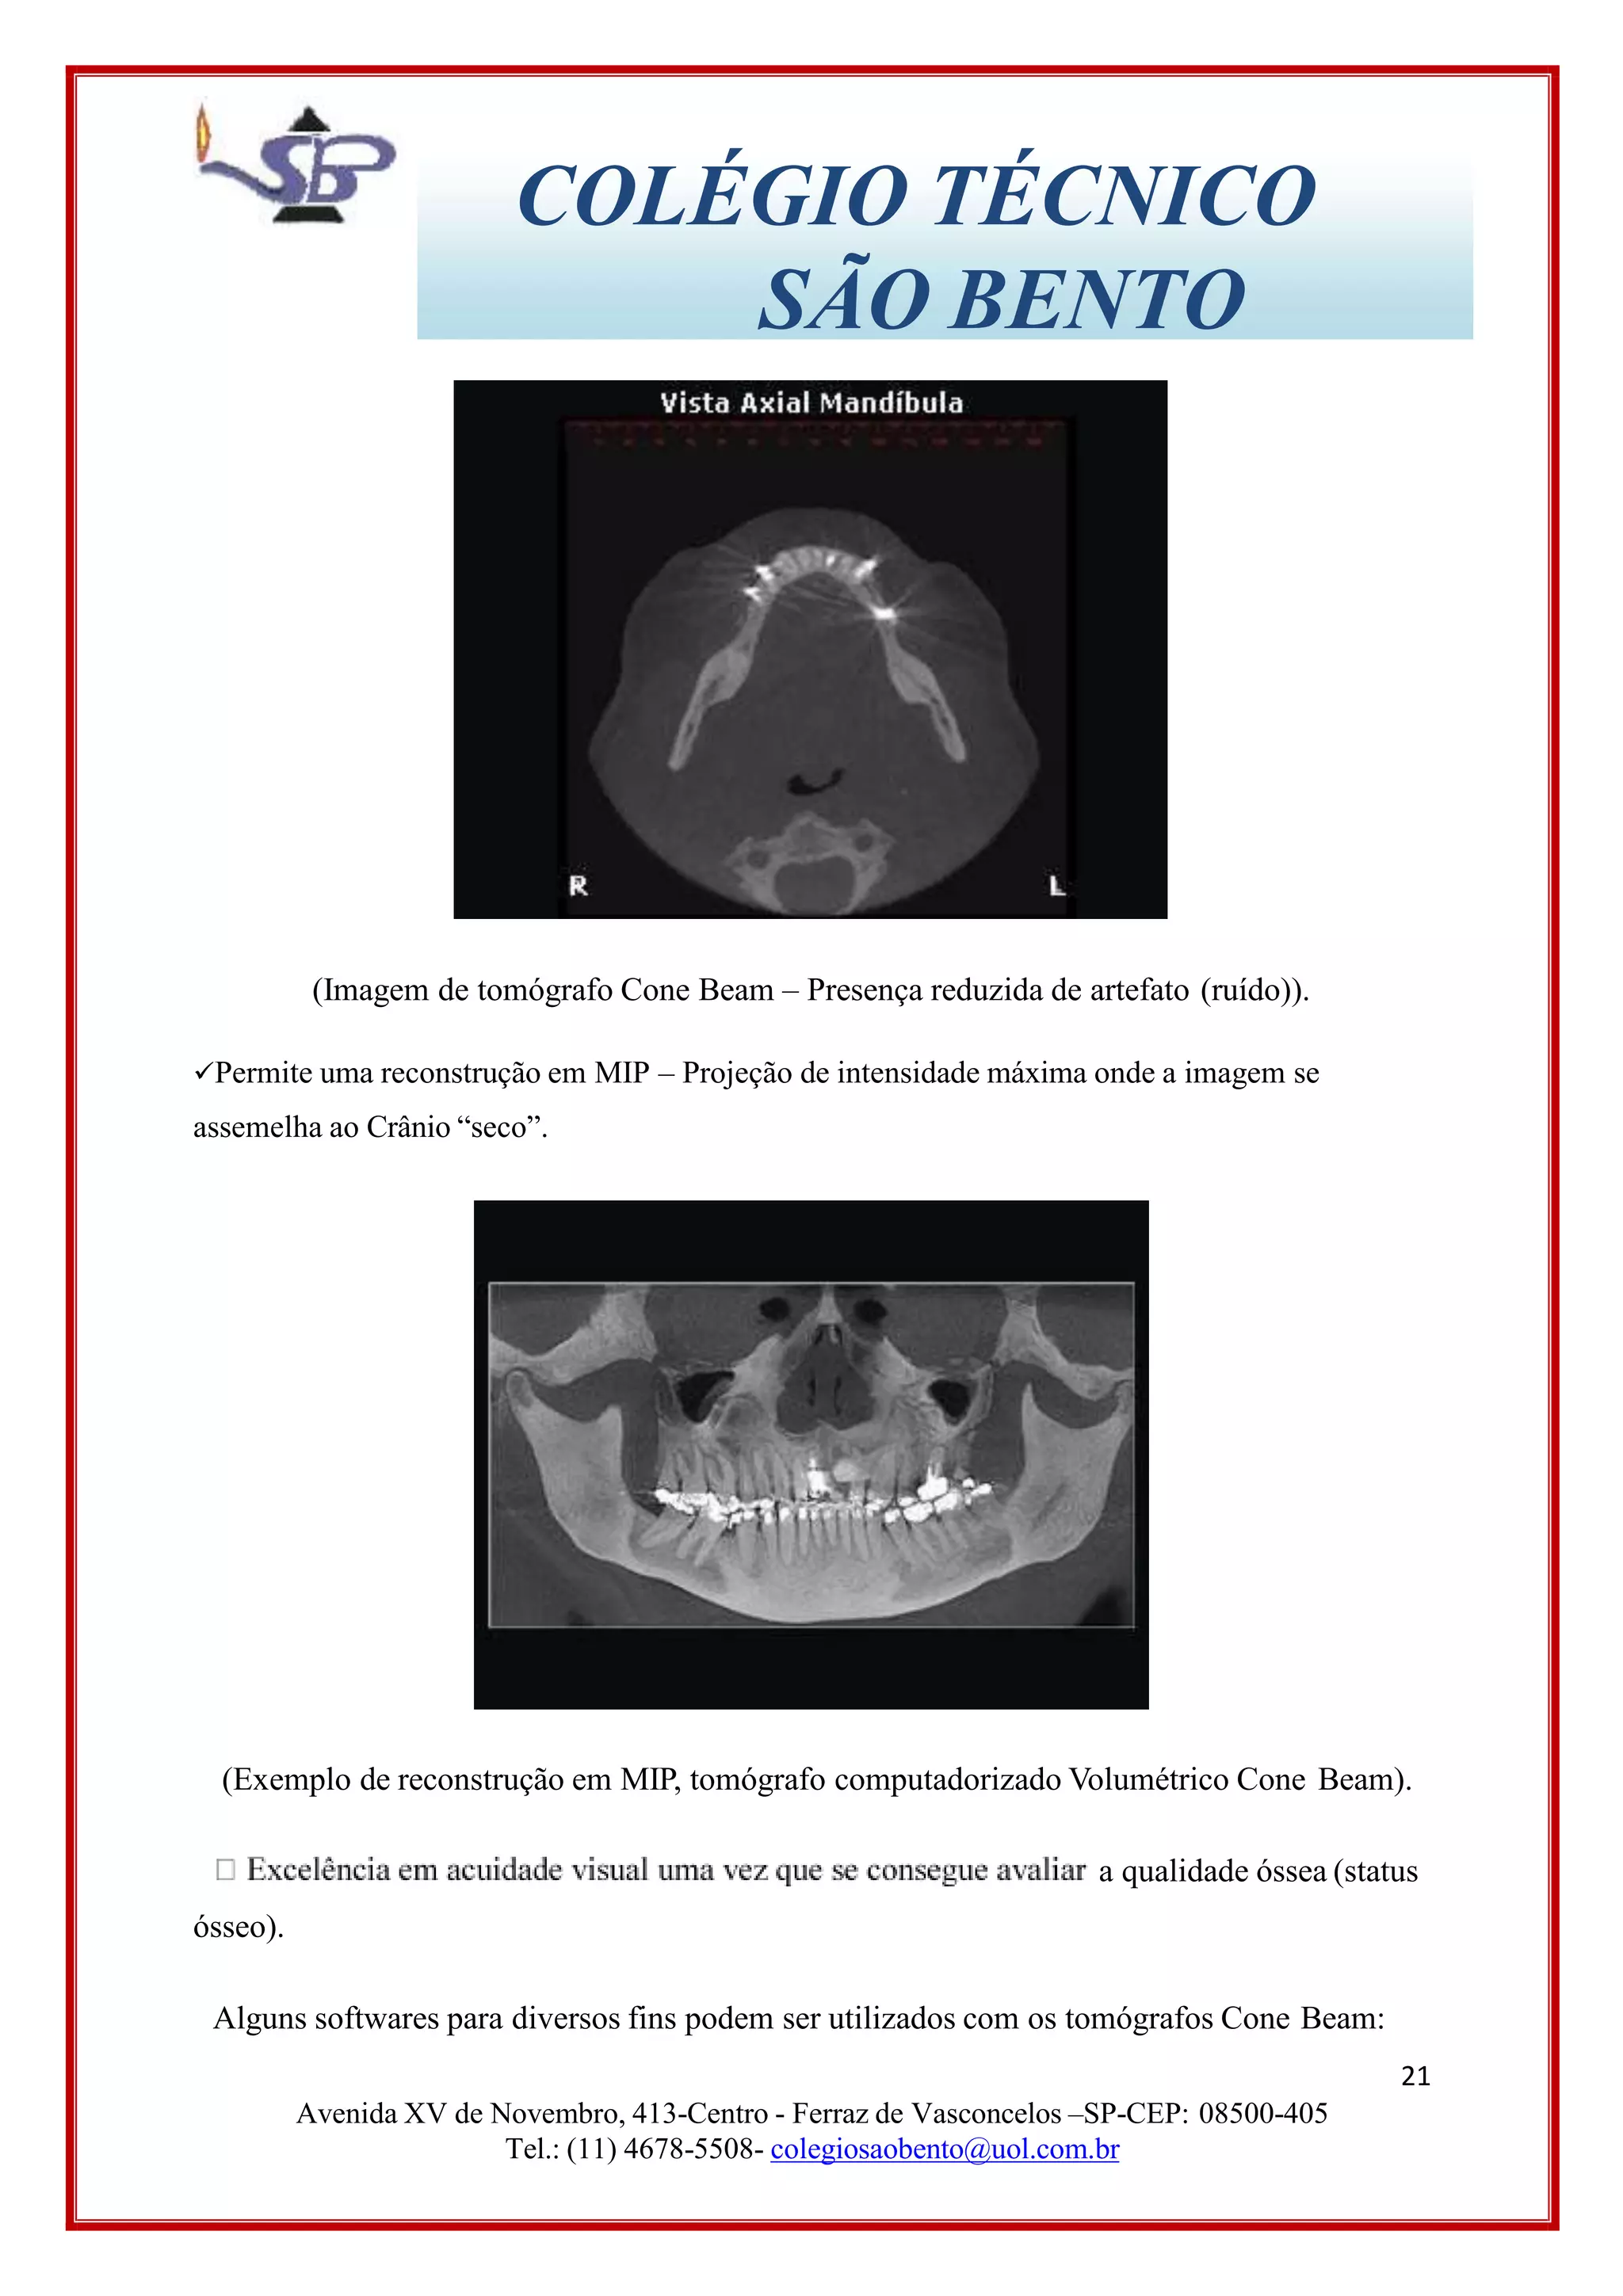

em tomógrafos computadorizados convencionais. Consequentemente permite a presença de

metais (restauração, prótese, núcleo, aparelho ortodôntico) na tomada.

(Imagem de tomógrafo Cone Beam – Presença reduzida de artefato (ruído)).

Permite uma reconstrução em MIP – Projeção de intensidade máxima onde a imagem se

assemelha ao Crânio “seco”.

(Exemplo de reconstrução em MIP, tomógrafo computadorizado Volumétrico Cone Beam).

a qualidade óssea (status

ósseo).